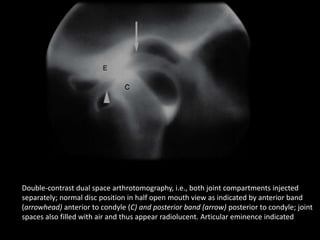

Double-contrast dual space arthrotomography, i.e., both joint compartments injected

separately; normal disc position in half open mouth view as indicated by anterior band

(arrowhead) anterior to condyle (C) and posterior band (arrow) posterior to condyle; joint

spaces also filled with air and thus appear radiolucent. Articular eminence indicated